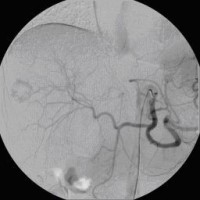

Superselektive transarterielle Chemoembolisation (TACE) mit Sondierung eines tumorversorgenden Gefäßes 1

(Bild 3 von 5)

Superselektive transarterielle Chemoembolisation (TACE) mit Sondierung eines tumorversorgenden Gefäßes 2

(Bild 4 von 5)

Superselektive transarterielle Chemoembolisation (TACE) mit Sondierung eines tumorversorgenden Gefäßes 3

(Bild 5 von 5)